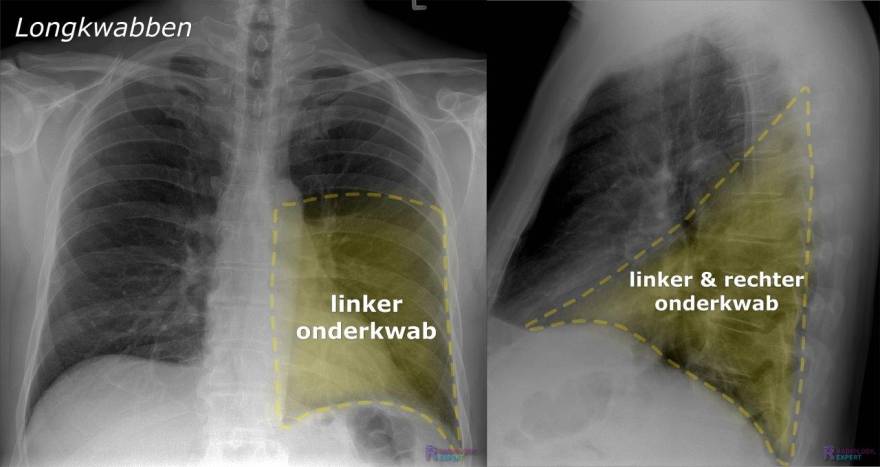

Het antwoord op de vraag is dat de rechterlong drie kwabben heeft, en de linkerlong twee. Waarom? Omdat het hart wat ruimte inneemt aan de linkerkant. Dit is al een perfect voorbeeld van hoe verschillende delen van je lichaam samenwerken en elkaar beïnvloeden. Het is teamwork op z’n best!